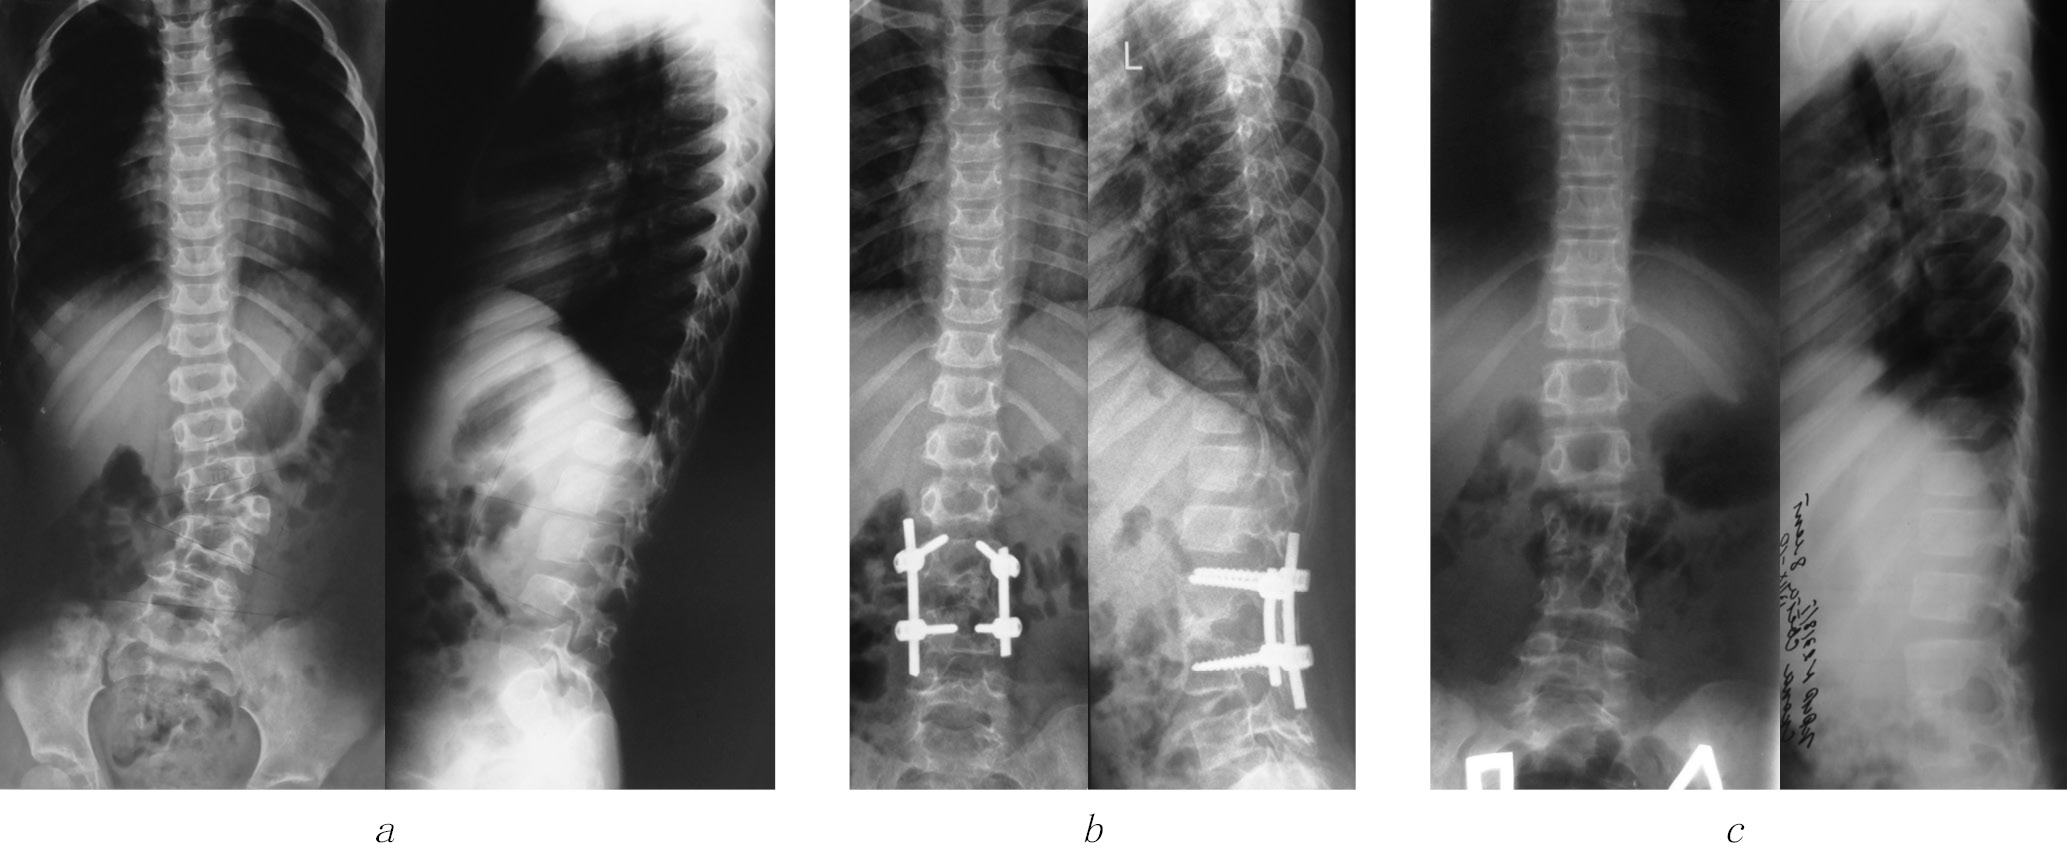

After surgery in patients of both groups, a radical correction of both the scoliotic and kyphotic components of the deformity was achieved with the restoration of physiological profiles of the spine. The insignificant residual value of the deformity, as well as the difference in the measurement of correction indicators between the groups and in the long-term follow-up period, corresponded to the values of the measurement error. As a result of the surgery, it was possible to restore the sagittal profile of the deformed spinal motion segment (Figure).

Radiographs of patient K., 1 year and 3 months, with congenital kyphoscoliosis with posterolateral semivertebra: (a) before surgery, the scoliosis angle is 26°, and the kyphosis angle is 12°; (b) 1.5 years after the surgery from a combined approach; and (c) 6 years after removal of surgical hardware

However, in the long-term period after surgery, a progression of the kyphotic component of the deformity in the lumbar spine from –19° to –8° (p = 0.04) was noted in the group of patients operated only from the dorsal access, while the correction value of the scoliotic component of the curvature remained stable throughout the entire period. At the same time, it should be noted that the achieved correction of deformity after surgery remained stable during the long-term follow-up period in patients using a combined approach. During the surgery, correction was achieved by stabilizing a larger number of vertebrae in Group 1 compared with that in the comparison group. This result was because dorsal access did not provide a sufficiently good and complete visual view and achieve full mobility in the intervention zone. The results are presented in Table 4.